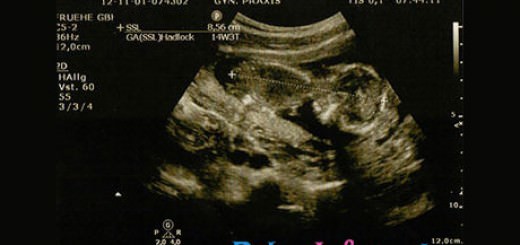

Eine von euch engagierte Beleghebamme kümmert sich um Vorsorge, die Geburt und die Nachsorge nach Ihrer Entbindung. Außerdem kann man bei Hebammen einen Geburtsvorbereitungskurs absolvieren. Die Hebamme führt oft auch Untersuchungen während der Schwangerschaft, parallel oder im Wechsel mit dem Frauenarzt, durch. Dabei handelt es sich zumeist um einfache Untersuchungen wie Bestimmung des Gewichtes, Messen des Blutdrucks und Kontrolle des Urins. Die Hebamme tastet auch den Bauch der Mutter ab, um die Lage des Kindes zu bestimmen. Kurz vor der Geburt wird mehrmals eine Kardiotokografie (kurz CTG) durchgeführt. Bei dieser Untersuchung werden die Herztöne des ungeborenen Kindes überwacht, um eventuell auftretende Unregelmäßigkeiten zu erkennen. Außerdem gibt das CTG auch Aufschluss über evtl. schon einsetzende Wehentätigkeit.